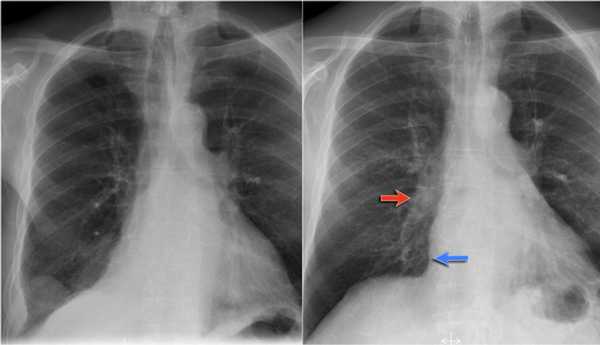

Но случаются ситуации, когда мы не видим никаких изменений, как на обзорной рентгенограмме в данном случае: практически легочные ткани. Но, посмотрите - корень левого легкого располагается на одном уровне с корнем правого легкого. Это позволяет нам предположить, нет ли тут какого-то процесса, который приводит к уменьшению объема.

На боковой рентгенограмме мы видим ателектаз язычковых сегментов, который в данном случае скрыт за тенью сердца. Именно этот процесс и вызывает смещение корня легкого.